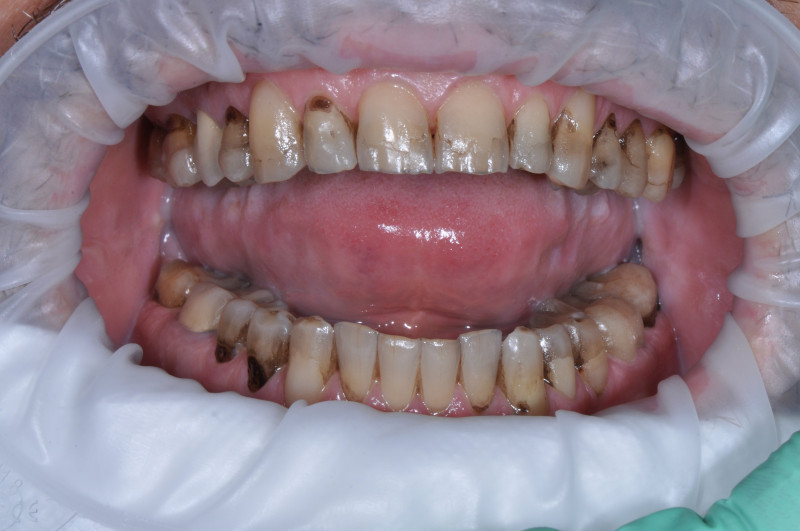

На странице представлено портфолио стоматологий Москвы с работами до и после профессиональной чистки зубов. В нашем портфолио собраны разные клинические случаи: от удаления незначительного налета до снятия массивного поддесневого камня. Здесь вы можете увидеть, как возвращается естественный цвет и внешний вид зубов после процедуры. Изучите результаты до и после чистки зубов, чтобы увидеть реальный эффект и выбрать клинику в Москве, где профессиональная гигиена поможет вернуть зубам здоровый вид.

Профгигиена

Пациентка регулярно приходит за профессиональной гигиеной зубов и полости рта

Доктор: Карапетян Фреда Сергеевна